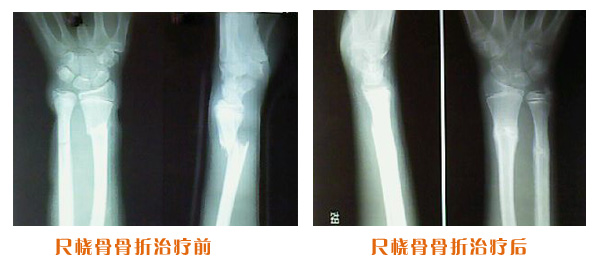

肥城市安駕莊梁氏骨科醫(yī)院是一所以梁氏手法正骨配合膏藥為特色的現(xiàn)代化專科醫(yī)院。

梁氏骨科術(shù)始創(chuàng)于清雍正年間,歷經(jīng)八代,至今已有三百年歷史。據(jù)1929年泰安縣志載“梁瑞圖先生,字增生,號蓮峰,安駕莊人,精岐黃并發(fā)明接骨,凡跌打車凡跌打車軋皮不破而碎骨者......【詳細】 |